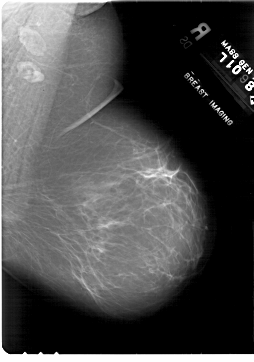

A_1818_1.LEFT_MLO

LEFT_MLO LINES 6676 PIXELS_PER_LINE 5116 BITS_PER_PIXEL 12 RESOLUTION 43.5 OVERLAY